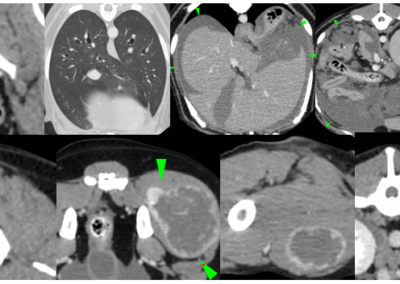

Oncologie

Caractérisation des tumeurs, bilan d’extension, planification chirurgicale.

Thorax

Epanchements pleuraux et médiastinaux, fibrose pulmonaire, torsion de lobe, pneumonie, pneumomédiastin, bilan d’extension des tumeurs.

Abdomen

Exploration des tous les organes abdominaux, malformations vasculaires (shunt, anévrysme), uretère ectopique.